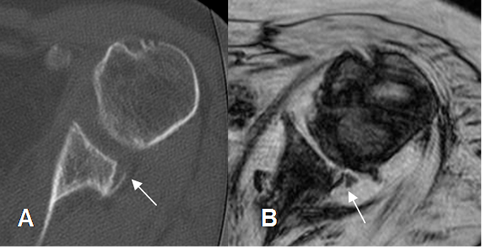

Fig 72 B. Lesión de Bankart posterior.

A: TAC axial. Fractura en la glenoides posterior.

B: RM axial en FFE. Ruptura del labrum y la glenoides posterior por Bankart óseo invertido.